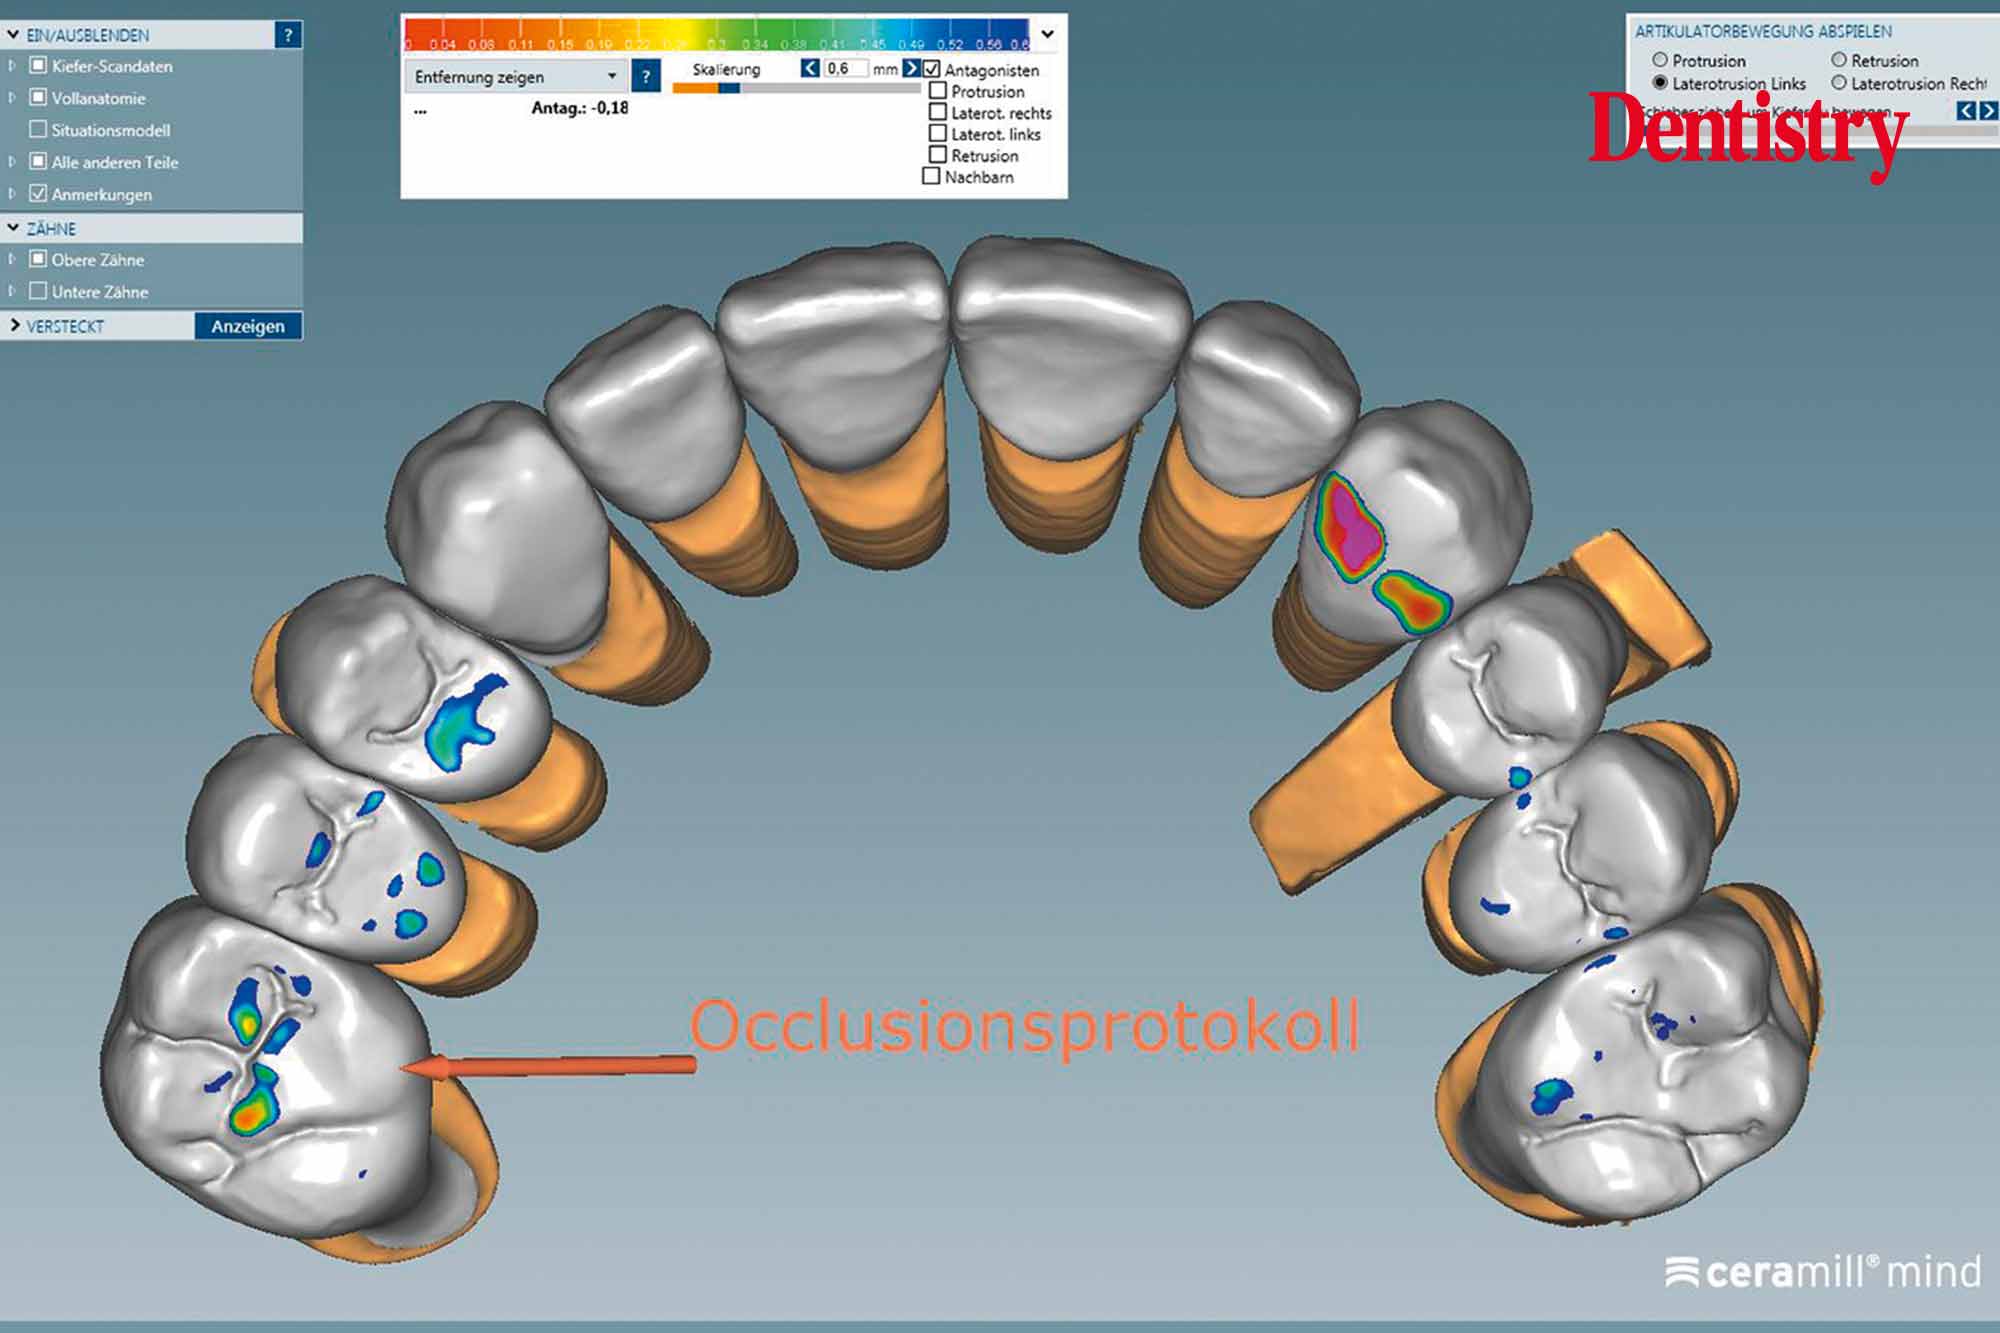

Canine guidance with a light group function was created on the Ceramill Mind Wizard.

Utilising CAD/CAM software including its virtual articulator allowed us to fabricate full mouth crowns with guaranteed success.

As well, monolithic zirconia crowns do not exhibit roughness if glazed properly, and therefore end up being kind to their antagonist teeth (Figures 16 to 24).